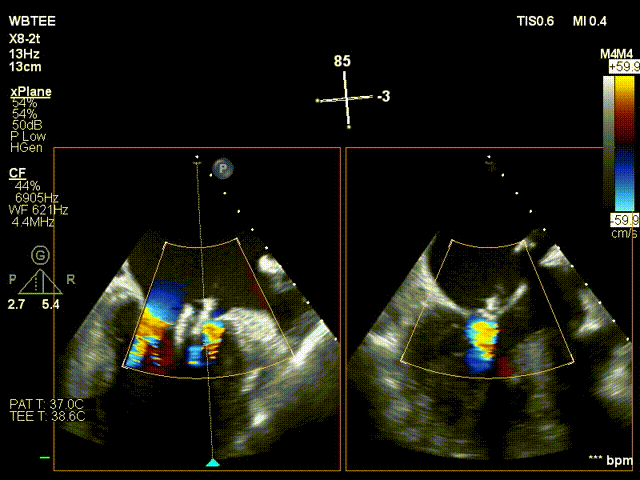

在食道超声王蓓主任的紧密配合下,经食道超声引导后傅国胜教授使用二尖瓣夹准确成功捕获前叶A2和后叶P2反流最严重区域,并予夹合,使二尖瓣在收缩期由大的单孔变成小的双孔,显著减少了二尖瓣反流。

反复测试二尖瓣钳夹的稳定性,超声复查提示二尖瓣夹内侧反流有效改善,外侧仍有部分反流,平均跨瓣压差2mmHg,肺静脉收缩期逆流频谱恢复正向,傅国胜教授团队与超声影像团队充分沟通讨论,计划在二尖瓣夹外侧再置入第二枚二尖瓣夹,遂精准释放第一个二尖瓣夹。

傅国胜教授继续在食道超声影像引导下进行高难度操作,在第一个二尖瓣夹外侧再置入第二枚二尖瓣夹NTR。

再次反复测试第二枚二尖瓣钳夹的稳定性,超声复查提示二尖瓣反流明显改善,平均跨瓣压差4mmHg。